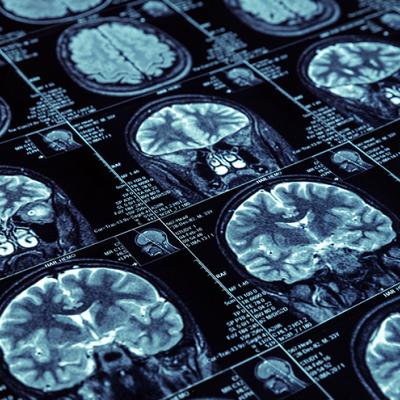

Une nouvelle décevante concernant un nouveau traitement potentiel de la maladie d’Alzheimer

La Société Alzheimer du Canada est déçue d’apprendre qu’après examen des données des essais cliniques de la phase 3, le groupe consultatif de la Food and Drug Administration (FDA) américaine n’avait trouvé aucune preuve formelle permettant d’indiquer qu’un nouveau traitement potentiel pour la maladie d’Alzheimer était efficace pour réduire le déclin cognitif.